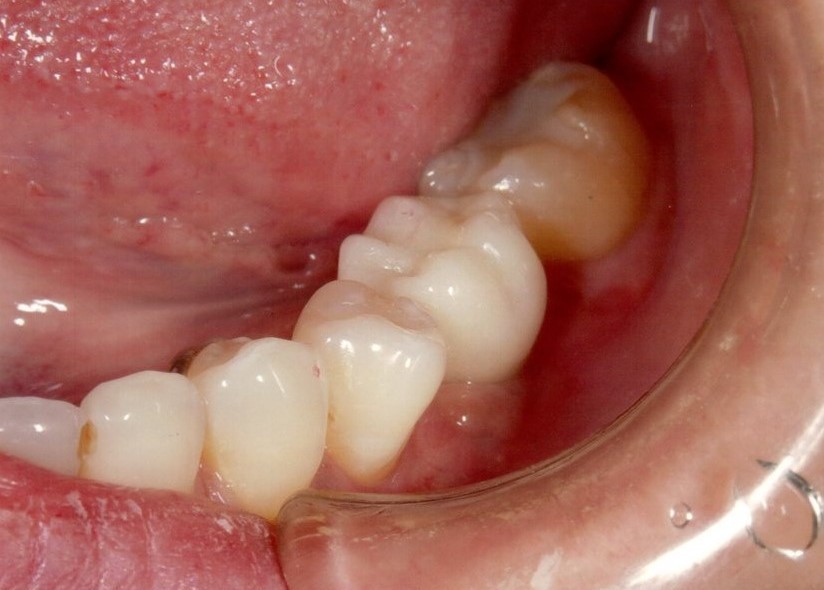

奥歯インプラント(スクリュー固定)

(伊東市 女性)

治療の流れ

むし歯で歯を失ってしまいました。

インプラントを埋入し、最終的な被せ物を装着しました。(ネジ穴をふさぐ前)

ネジ穴をふさぐとこの様な状態になります。

インプラント手術:250,000円

静脈内鎮静法:0円

既製アバットメント:90,000円

メタルボンド:130,000円

総額:470,000円+税